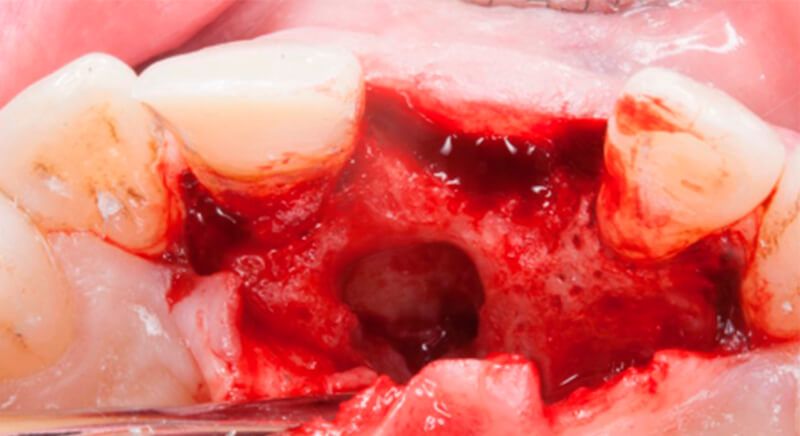

Once tooth 2.1 had been extracted, it was decided that it was not advisable to place an implant immediately as the bone conditions were not ideal and the gum did not have sufficient thickness. We opted for a treatment to preserve the socket and to delay implant insertion.

The socket was filled with a xenograft after the extraction and a graft of connective tissue was placed in the vestibular area of the two upper central incisors.